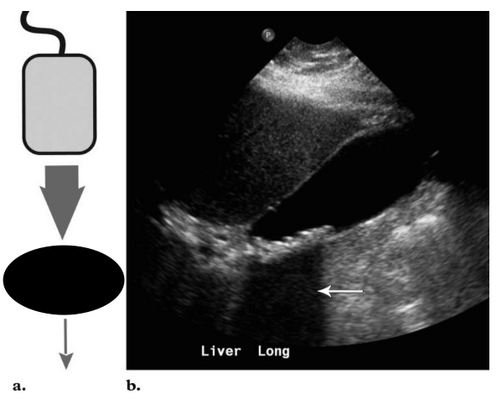

4. Зеркальное отражение

Этот артефакт, возникает на границе двух сред (поверхность диафрагма - лёгкие и поверхность перикард - лёгкие). Механизм этого явления заключается в том, что на границе раздела сред часть луча проходит через неё, а часть - отражается. Отраженные лучи возвращаются на трансдуктор и формируют ложное изображение(1;5).

Примером артефакта зеркального отражение в норме является появление ложного изображения паренхимы печени и второго желчного пузыря за пределами диафрагмы. Такое изображение важно трактовать не как нарушение целостности диафрагмы и не как «двойную» печень.

Артефакт зеркального отражения может быть ультразвуковым маркёром патологий, при которых существенно повышается плотность мягких тканей, например, местного или генерализованного «сухого» перитонита.